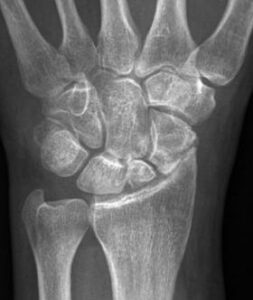

Radiografie van polsarthrose ten gevolge van niet geheelde breuk (links) of (onbehandeld) ligamentair letsel (rechts)

De diagnose van een polsarthrose wordt meestal zo op de raadpleging gesteld. Typisch is het uitvoeren van een RX aangewezen. Soms kan een CT of MRI nuttig zijn om de diagnose fijn te stellen.